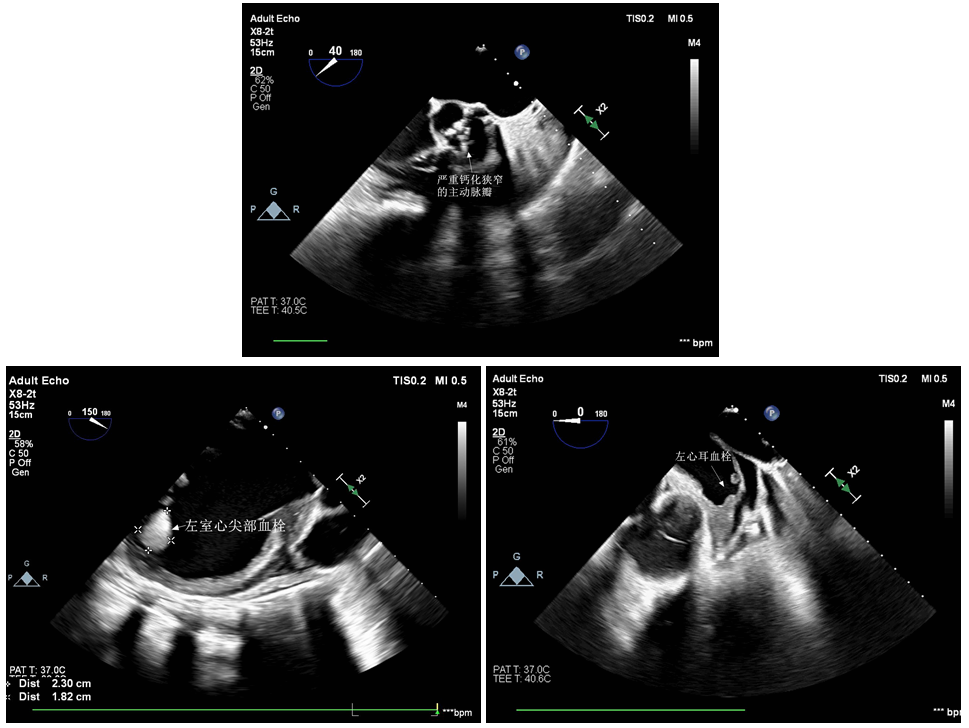

62岁的黄阿姨患重度主动脉瓣狭窄,近半年反复胸闷、憋喘、不能平卧,多次住院药物治疗,心衰始终难以纠正,生活质量极差,时刻面临着死亡的威胁。1个月前,黄阿姨到省立医院就诊,超声心动图显示LVEF仅20%,外科手术风险极高,TAVR成为最佳的手术选择。但黄阿姨左心耳及左心室存在血栓,尤其是左室心尖部的2.3*1.8cm的附壁血栓,在实施TAVR过程中一旦脱落,可能造成致命的血栓栓塞事件。心内科心衰团队为黄阿姨制定了周密的治疗方案,经过半个月的优化药物治疗,黄阿姨心功能改善得以出院,期待继续抗凝治疗后患者心腔血栓能够消失,择期入院行TAVR。

计划赶不上变化,出院半个月,黄阿姨感冒后心衰急性加重,来到东院心内科病房时已是全身浮肿、四肢湿冷、一息尚存,急诊TAVR刻不容缓。在心内科主任苑海涛教授组织协调下,一方面心衰团队积极纠正患者心源性休克,为准备手术争取时间;另一方面王勇主任医师带领TAVR团队联合心外科、麻醉手术科、超声医学科、ICU等科室商讨手术方案与细节。黄阿姨心功能极差,术中循环崩溃的风险很高,心腔内血栓飘飘欲坠更是增加了手术的风险与难度,国际国内鲜有左心室血栓急诊TAVR的经验可以参考,这绝对是一台极具挑战的抢救性手术!